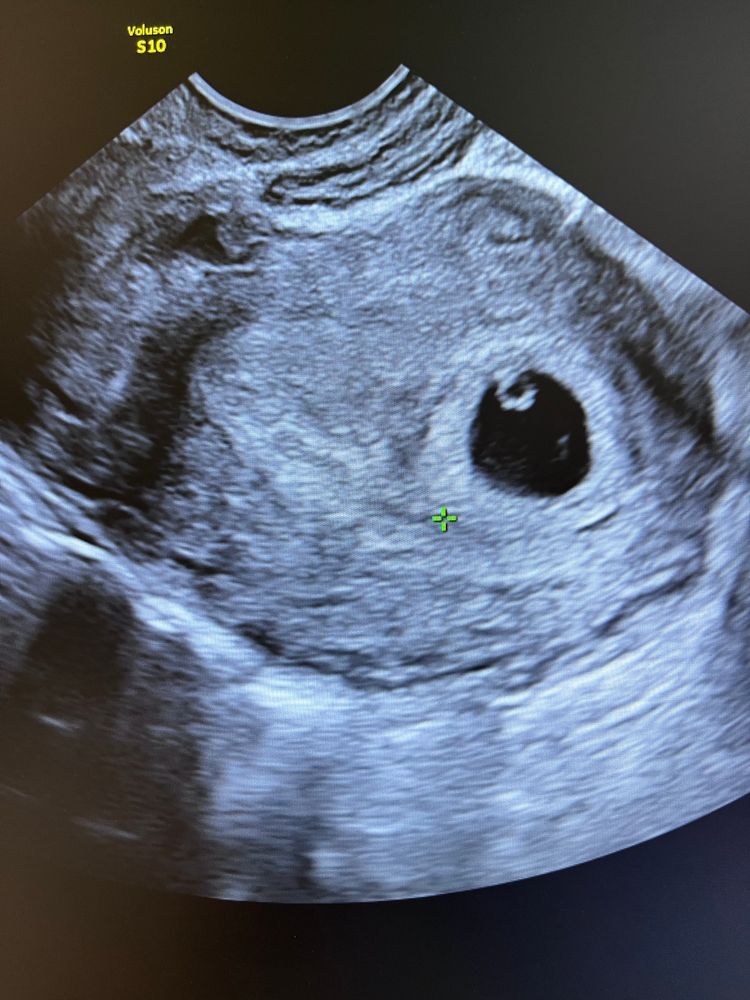

Всем привет девчонки. Вчера ещё узнавала у вас на счёт коричневых выделений, надеялась что всё хорошо будет и не может быть внематочной. Сколько проверок,УЗИ, анализов... Но судьба решила по другому, сегодня мне подтвердили ВБ. Снова ВБ, ровно год спустя. Я просто разбита...за что такое наказание... 5-6 недель... Снова приходить в себя 2-3 месяца и снова сдавать анализы... Я как хотела так и сделаю, я готова на ЭКО. Последняя моя надежда ЭКО😢

Лили, ХГЧ 1430-1600,в матке пусто. Плюс с левой стороны болит.

Мила, подождите, но где-то ещё тоже не видно? По идее в трубах на этих цифрах уже, наверное, должны увидеть...

у меня на 5-6 неделе тоже был такой хгч, тоже болело в боку и тоже ничего не видно было на узи